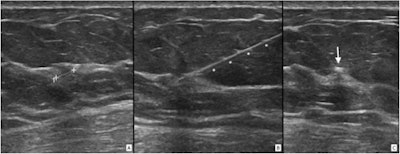

For their prospective study, Depretto and colleagues wanted to evaluate the performance of preoperative magnetic seed localization on nonpalpable breast lesions, using the Magseed system (Endomag, Endomagnetics). This system includes an ultrasound localization device that uses a stainless-steel magnetic seed that's deployed with an 18-gauge needle.

The researchers tested the system by placing a total of 1,123 magnetic seeds in 1,084 women. Four radiologists placed the seeds under ultrasound or stereotactic guidance.